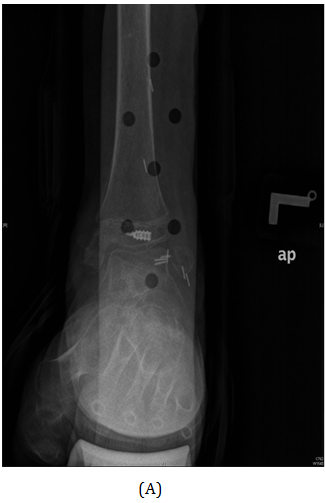

A Saudi girl, 10 years old presented to OPD with progressive swelling of the right ankle for 3 months, localized on the lateral aspect, and increasing with pain and swelling within last two months. During physical examination, proximal area of the skin over the swelling was dark black as what was noted. The patient was investigated primarily in a hospital outside of Riyadh according to a biopsy was taken with osteomyelitis of distal fibula and treatment was start taken but with no response. X-ray of the right leg (Figure 12) and CT of the lower limb (Figure 13). An expansile, lytic and destructive bone lesion is seen involving the distal third of the right fibula. (Figure 14) on MRI showed there is a large destructive bone lesion involving the distal third of the right fibula with sparing of the distal fibular epiphysis. No definite involvement of the right tibia and talus. Trace of fluid is seen in the right tibiotalar joint most likely reactive. The neurovascular structures appear intact. This was followed by technetium-99m MDP scintigraphy (Figure 15), what it showed a solitary focal lesion distal end of right fibula compatible with suspected Ewing's sarcoma. No additional lesions were noted to suggest skip lesions or metastasis. She treated as per Ewing sarcoma protocol in our hospital. Patient was put on neoadjuvant chemotherapy. Later, We did a wide surgical resection of the tumor was preformed upto12 cm from the distal fibula malleolus during which ,the superficial peroneal nerve and peroneus longus and brevis tendon were sacrificed the ruminant of the peroneus longus and calcaneo fibular ligament were sutured and using anchors were attached to the distal tibia in the right leg free pedicle latissmuss dorsi flap was anastomosed to the peroneal artery locally to cover the soft tissue defect by the plastic surgery team. The last MRI done for the patient (Figure 16) showed there is interval reduction in the size of the previously noted heterogeneous enhancing mass at the distal metaphysis of the right fibula. On the bone scan (Figure 17), there is interval reduction in the size of the previously noted heterogeneous enhancing mass at the distal metaphysis of the right fibula. There is no sign of skip metastases to other limb. Bilaterally bone marrow signal changes are most likely related to chemotherapy. The patient will follow up with us regularly.

Figure 12 AP view of plain X-ray of the right leg showed ill-defined lesion involved distal end of the fibula (diaphysis) with cortical destruction and soft tissues swelling.